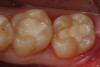

Fig 14. An occlusal view of the completed composite restorations on teeth Nos. 18 and 19.

Figure 14